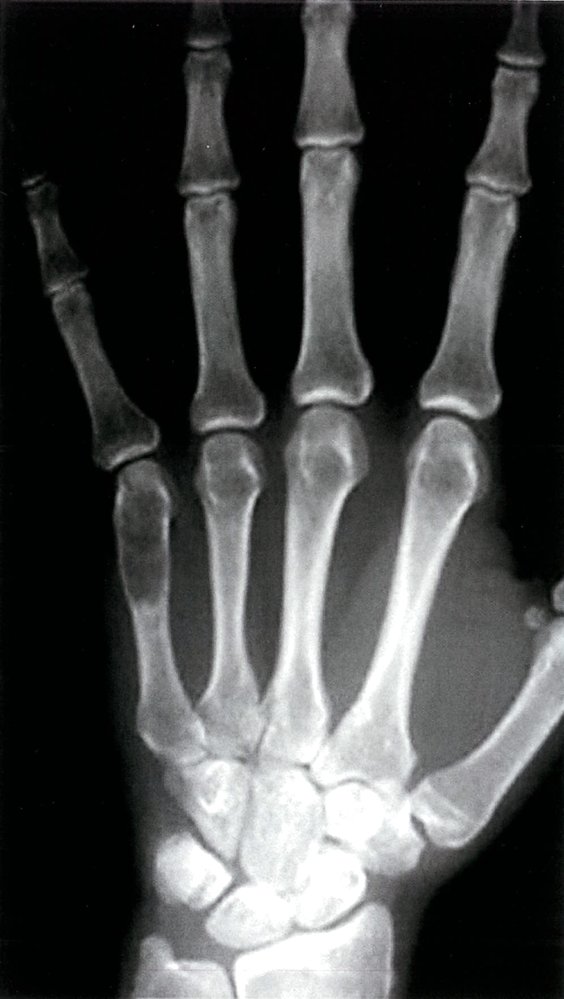

• Description: benign tumor arising from hyaline cartilage

• Epidemiology

• Most common type of hand tumor

• Peak incidence: 20–50 years (but may occur at any age)

• Clinical features

• Usually found in medulla of the long bones of the hands and feet (most often the metacarpals of the hand and phalanges of the fingers)

• Often painless

• Widening of the bone

• Pathological (spontaneous) fractures

• Subtypes and variants: enchondromatosis [3]

• Definition: A predominantly hereditary condition that manifests with multiple enchondromas.

• Epidemiology: peak incidence between 10 and 20 years

• Clinical features: often leads to skeletal deformities and stunted growth

• Prognosis: increased risk of malignant degeneration to chondrosarcoma

• Treatment

• Asymptomatic tumors do not require treatment and close monitoring suffices.

• Symptomatic tumors may require surgical curettage and subsequent bone grafting to prevent pathological fractures.